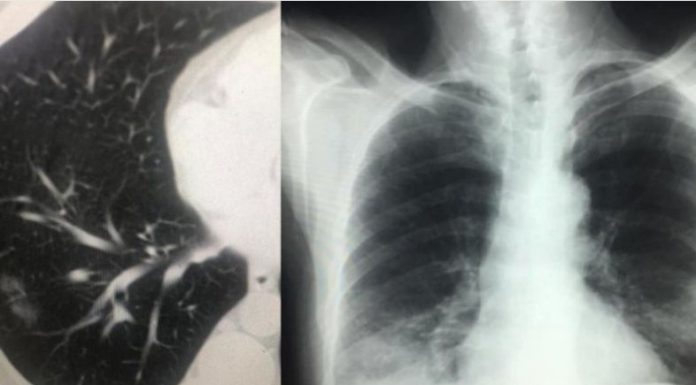

IMAZHET E JANARIT QË FLASIN PËR PREZENCËN E COVID-19 NË SHQIPËRI QË NË KËTË PERIUDHË

Sot, falë mikut dhe kolegut tim të nderuar Dr. Renato Osmenaj…, imazhëristit që ishte i pari, që që javën e parë pas zbulimit të të ashtuquajturit rast 0, identifikoi fizionominë dhe identitetin imazhërik pulmonar të COVID-19… dhe potencën e ekzaminimit CT ndër ekzaminimet e skemës bazë për diagnostikim dhe përcaktim prognose…, mu ofruan imazhe të pakundërshtueshme të prezencës së COVID-19 në datat 15 – 20 janar, në disa raste në Infektiv…!!! Dhe s’kishte si të ndodhte ndryshe, kur duam s’duam ne, për komunikimet e ngushta dhe lëvizjet e shumta njerëzore me Italinë e Veriut, Shqipëria mund të kosiderohet lagje e Milanos…!!!

Tani i takon Komitetit të Teknik të marrë serizisht këto fakte, për përcaktimin e një strategjie të qartë dhe të shpejtë zhbllokuese, për kalimin nga izolimi në distancim, duke kthyer në normalitet brenda një edukate distancimi jetën sociale, ekonomike dhe shëndetësore në vend…!!! Faleminderit Dr. Renato…, jo vetëm për menaxhimin pa panik, por me vigjilencë të situatës së karantinës, nëpërmjet centarlizimit dhe koordinimit nacional imazhërik për suspektim sa më të hershëm të sëmundjes dhe prevenimin e kaosit, që mund të kish shkaktuar strategjia e gabuar e numrit 127…, por edhe për ndihmën që po jep për Komitetin Teknik për konfuzionin në pritjen e pikut epidemiologjik…!!! Po ju ofroj pamjet imazhërike të pesë rasteve, duke ju kujtuar që janë pronë intelektuale e Dr. Renato Osmani dhe i publikoj me aprovimin e tij, duke mbrojtur të drejtën e tij të aitorit…!!!